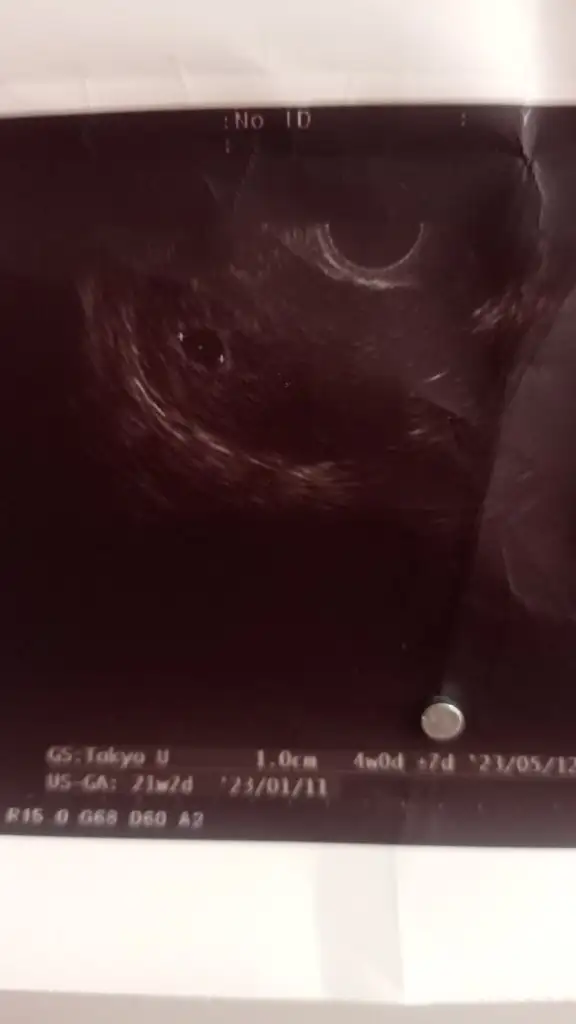

Benim kafam hiç almadı bu durumu yahuKizlar üstten belli olmadi yine alttan baktı bi kesenin icinde bebek görünmüyor dedi sonra diğerinde gozukuyormu onu soylemedi aha erken olabilir dedi bebek icin gerekli seyler olusmaya başlamış dedi 4 haftalik gorunuyor kesen dedi aklim karisti yani kalp atisi icin 10 gun sonraya cagirdi daha ama isin iyi yani tum kan testlerini yaptirdim herseye bakilmis oldu

bu ultrason karından mı yapıldı? Kaç haftalık dedi?

Galiba alttan muayenede daha net görünüyor benimki çokk uzaklardan görünüyordu çünkü içini filan görmek mümkün değildi. Bu doktorlar benim kafamı karıştırıyor yahuÇok teşekkür ederimYok karından değil alttan muayene etti 5+6 dedi doktorların kullandıkları makineler farklı olabiliyor belki onunla bi ilgisi vardır..